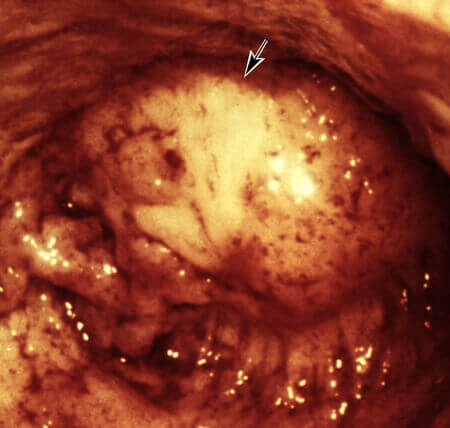

Además, pueden incluso destruir un cuerpo que parece joven y saludable. Yo diría que las muertes causadas por parásitos representan el 85 % de todas las muertes inesperadas o llamadas "súbitas". Mire estas fotos realizadas en nuestro laboratorio:

Cysticercus (tipo de parásito) en el cerebro humano (descubierto durante el transcurso de la cirugía, el paciente falleció):